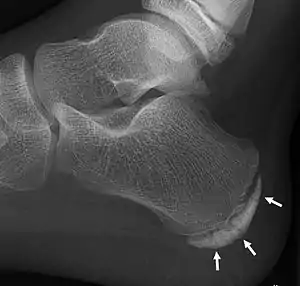

| X-ray of the foot of an 11-year-old child,showing sclerosis and fragmentation of the calcaneal apophysis. This is a sign of low sensitivity and specificity of Sever's disease, because those with Sever's disease may not have it, and this appearance is also present in feet without pain.[1] | |